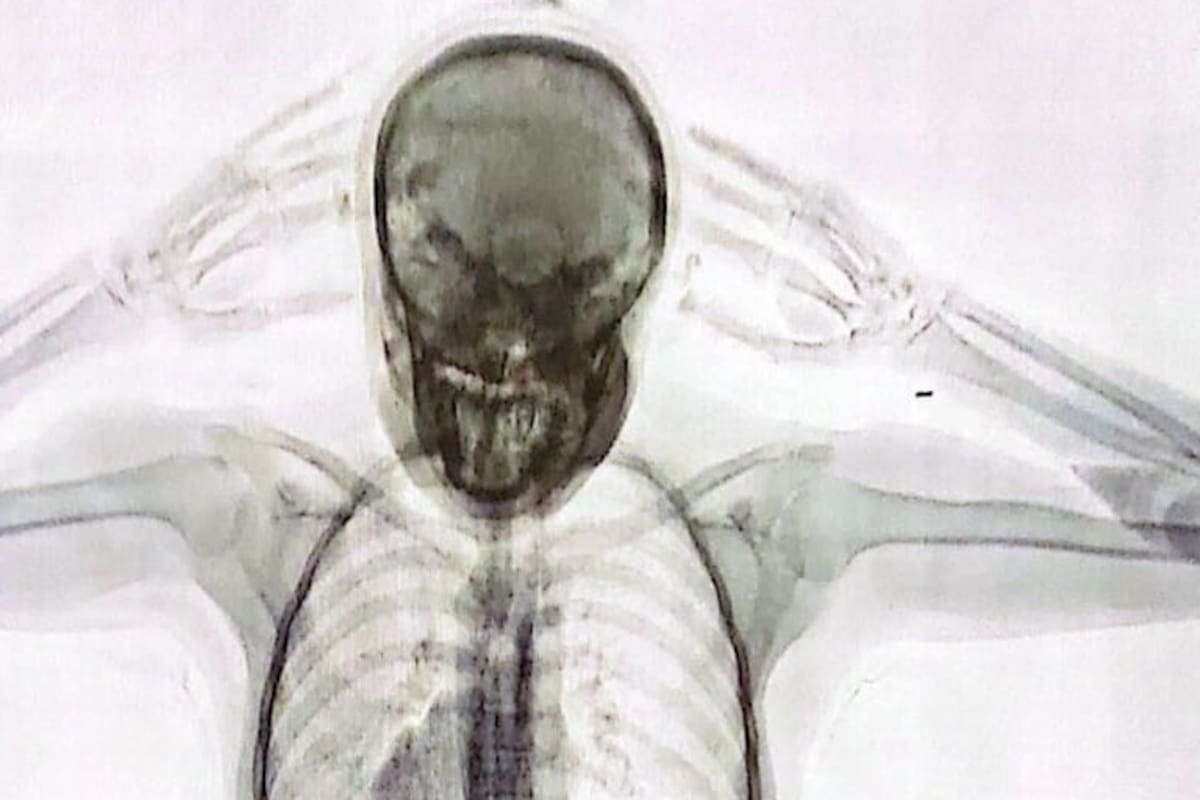

El joven, junto con un amigo, había llegado a la terminal de ómnibus de Retiro desde la ciudad de Córdoba. Su permanencia en Buenos Aires era cuestión de pocos días. Tenían previsto viajar a París, Francia, el 21 de julio pasado en un vuelo de Air France. Pero no pudo subirse al avión. Su nerviosismo en un control aleatorio de la Policía de Seguridad Aeroportuaria (PSA) y de la Dirección General de Aduanas lo puso en evidencia. Poco después, se descubrió que él y su acompañante eran “mulas” de una banda narco. Habían ingerido 110 cápsulas con cocaína. Si hubiesen llegado a destino, cada uno iba a recibir 5000 dólares a cambio del cargamento que llevaban en el cuerpo. Pero el frustrado plan puso al descubierto una sofisticada organización criminal dedicada al tráfico de estupefacientes desde la Argentina y Brasil hacia Europa y Asia.

Las “mulas” no siempre ingerían las cápsulas con cocaína en la Argentina. Según pudieron reconstruir los detectives policiales y judiciales, a veces, lo hacían en una escala en San Pablo, Brasil.